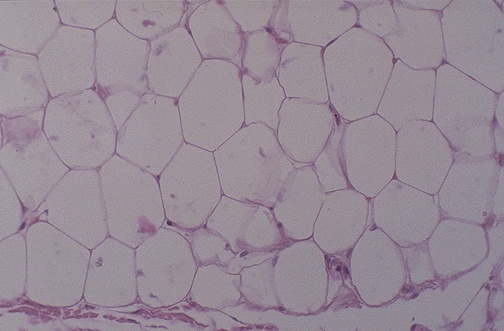

This is a lipoma. It is benign and tends to enlarge very slowly over time. Note how it is indistinguishable microscopically from normal adipose tissue. It is a neoplasm because grossly it formed a mass lesion.